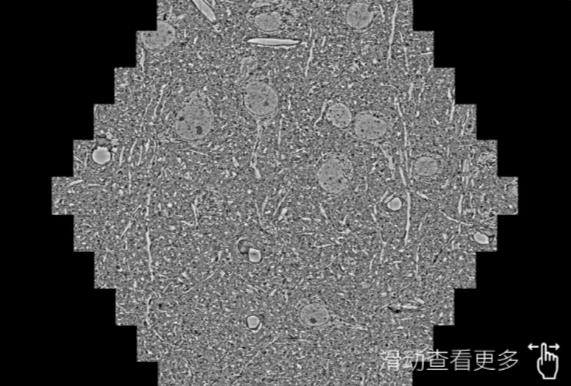

鼠脑切片。左图使用锡林郭勒蔡司锡林郭勒扫描电镜MultiSEM706对165μmx143pm面积区域成像,耗时仅需1.5秒。右图为鼠脑切片中30μm区域放大效果。样品由芝加哥大学B.Kasthuri提供。

使用蔡司高速锡林郭勒扫描电镜MultiSEM对1mm²人脑皮层组织进行高分辨成像,并对其中的各种细胞结构进行三维重构分析。左图展示了2x3mm²组织平面中锥体神经元的三维重构效果。右图显示了局部体积神经元三维重构。图像由哈佛大学chtman实验室提供,渲染图由D. Berger 制作。